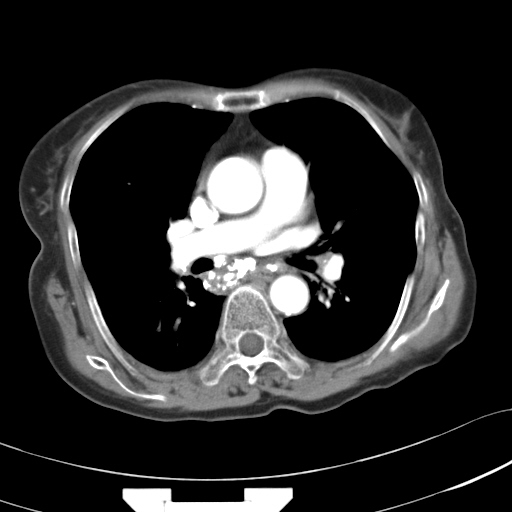

以下是引用hhcckk在2007-3-2 14:51:00的发言:[br]考虑结核球可能性大,依据[br]1病灶在下叶背段,结核的好发部位[br]2病灶内有大量的钙化,纵隔内有大量的淋巴结钙化[br]3重要的是半年前与现在相比无变化,假如是肿瘤的话不会这么‘善良’[br]4病灶周围卫星灶不明显,病灶有毛刺,胸膜凹陷,肿瘤不能完全排除,有条件的话最好做个活检

以下是引用liuyue在2007-3-2 17:15:00的发言:[br]1位置:右上叶后段[br]2性质:大分叶、粗长毛刺、条状斑片状钙化、纵隔多发淋巴结钙化,无强化,故考虑:肺结核灶(陈旧)